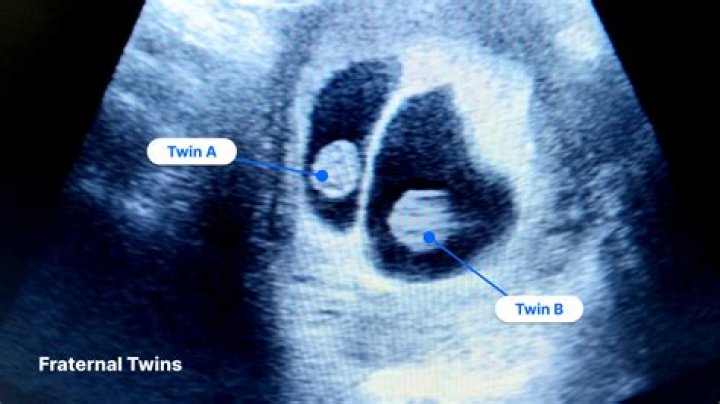

Can a twin hide behind the other in an ultrasound?

Technically, a twin can hide out in your uterus, but only for so long. It's not unheard of for a twin pregnancy to go undetected in early ultrasounds (say, around 10 weeks).

However, there is a very small chance that a twin can be missed on a scan, particularly during early pregnancy. Finding Out You're Expecting Twins In most cases, if you're expecting twins or more then you will find out as soon as you have your first ultrasound scan.

Babies don't have a lot of space to hide in. However, whilst uncommon, it's possible that a twin baby can hide on ultrasound by hiding behind its sibling in the sac. If a baby's feeling shy, they can go unseen if blocked by their sibling.

There's a very small chance that a twin may be hiding and missed during your first ultrasound (especially if you have it done earlier than 12 weeks). Chances of missing a twin are higher if they share the same amniotic sac.

It's possible to see twins (or more) on an ultrasound at around six weeks, though one baby may be missed at this early stage. Sometimes a heartbeat is seen in one sac, but not in the other. Rescanning in a week or two may reveal a second heartbeat, or the scan may show that one sac is growing and the other still empty.

Twins can be missed at 7 weeks or at any gestation. It's hard to believe but one gestational sac can hide behind another. One developing baby can be almost like a shadow of the other and difficult to detect. Heartbeats can be so in sync that it is hard to distinguish one from the other.